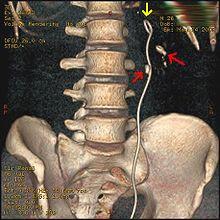

Three-dimensional reconstructed CT scan image of a ureteral stent in the left kidney (indicated by yellow arrow). There is a kidney stone in the pyelum of the lower pole of the kidney (higher red arrow) and one in the ureter beside the stent (lower red arrow).